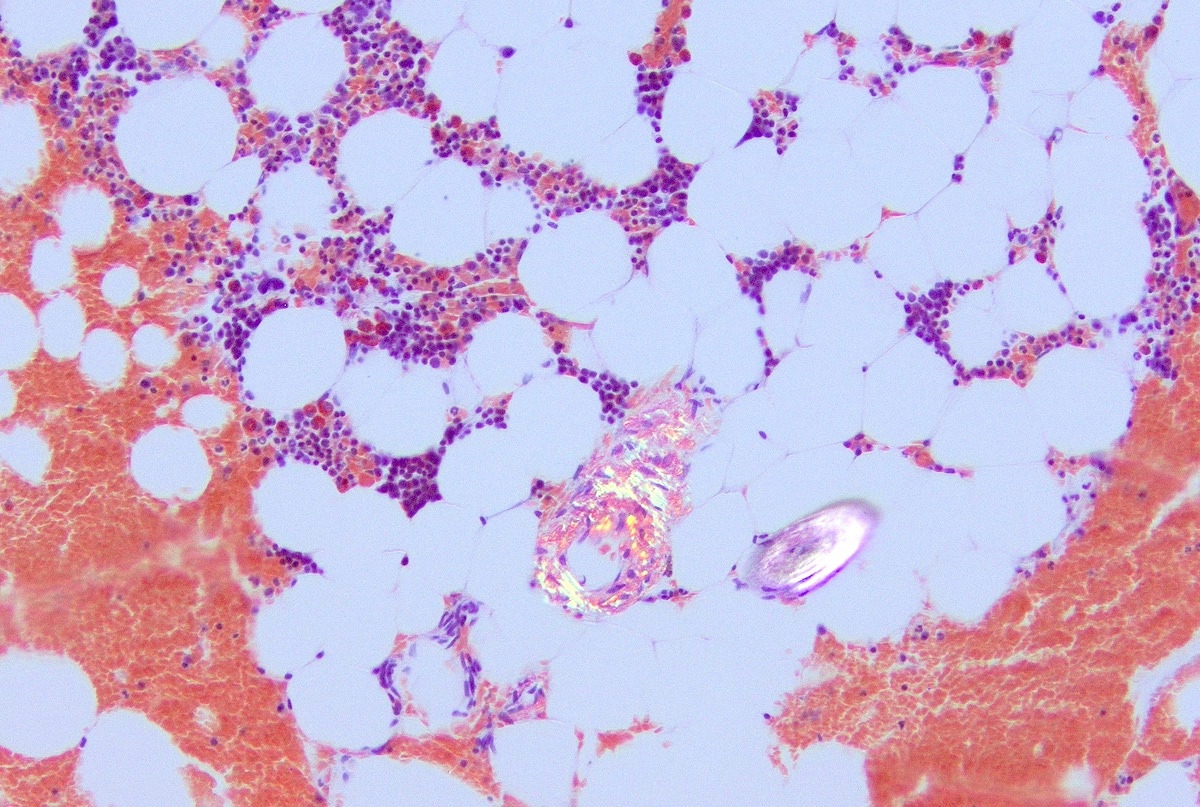

Microscopic (histologic) description

- Core biopsy (Am J Clin Path 1987;87:342):

- Interstitial clusters, nodules or sheets of plasma cells

- Areas of bone marrow may be spared with preserved hematopoiesis, other cases may have diffuse involvement and markedly suppressed hematopoiesis

- Prominent osteoclastic activity may be seen

- IHC to quantify plasma cells (CD138), stains for Ig kappa and lambda to establish clonality

Microscopic (histologic) images

Contributed by Genevieve M. Crane, M.D., Ph.D. and Tapan Bhavsar, M.D., Ph.D.